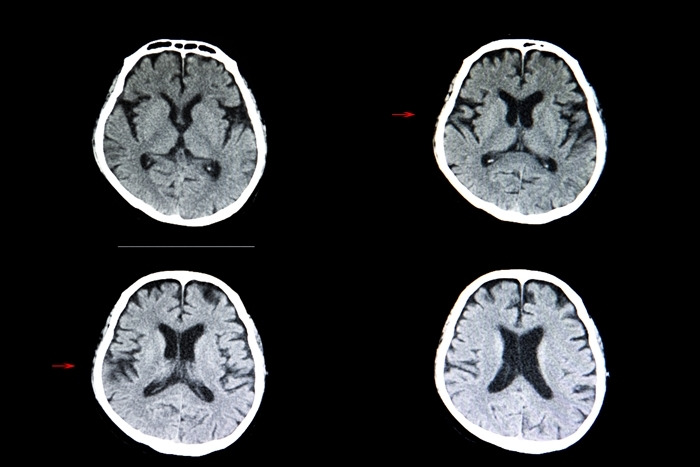

뇌경색은 뇌조직이 괴사돼 회복 불가능한 상태에 이른 걸 말한다.

뇌조직은 평소 많은 양의 혈액을 공급받는데, 다양한 원인으로 뇌혈관이 막혀 혈액량이 줄어들면 뇌조직이 정상적인 기능을 하지 못한다.

뇌혈류 감소가 일정 시간 지속되면 뇌조직이 괴사된다.